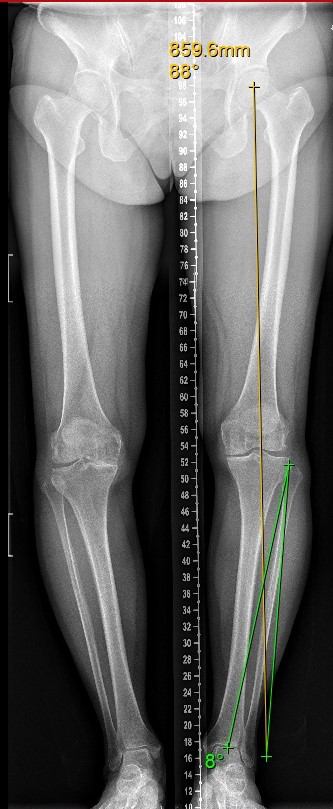

当人活动量过大,体重增加时,最容易损伤关节表面的软骨,导致骨性关节炎。而且关节软骨有一个特性,就是损伤之后很难修复。关节软骨损伤之后,它“减少摩擦、缓冲压力”的作用也会相应减弱。当膝关节负重时,约75%的载荷通过内侧间室,外侧间室仅有约25%的载荷。长期处于高负荷状态下的内侧间室软骨面逐渐退变、磨损,导致下肢力线向内侧偏移,加重软骨磨损,形成恶性循环,发展为膝内侧骨性关节炎。

—胫骨高位截骨术(high tibial osteotomy, HTO),是通过胫骨近端微创楔形开槽,改变下肢力线的异常分布,降低内侧间室的压强,将其恢复到软骨能够承受的正常范围,使得受损的膝关节内侧不负重或者少负重,可明显缓解疼痛和改善步态,改善膝关节生物力学环境和有效血液循环,促进内侧间室关节软骨修复,减轻膝关节疼痛,恢复膝关节正常活动。从而避免换关节,或者推迟换关节的时间。特别适合相对年轻活跃、MPTA(胫骨近端内侧角)小于85度或大于90度的内侧骨关节炎患者。临床实践证明,约三分之二的患者并不需要膝关节置换,可以采用保膝手术治疗,有效率甚至超过全膝关节置